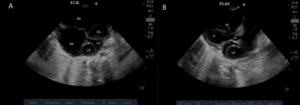

In an attempt to control the heart rate with verapamil, 5 mg was intravenously administered, and she spontaneously reverted to sinus rhythm after 4 hours. POCUS revealed dilatation of the coronary sinus to a diameter of 16 mm (Figure 1 and online Video S1). A phased-array 5-MHz ultrasound probe (GE Vivid S6N, N-3191 Horten, Norway) was used. Dilatation of the coronary sinus raised our suspicion of persistent left superior vena cava (PLSVC). In addition, POCUS revealed no echo drop-out in the interatrial, septum, normal size, or systolic function of the left ventricle (LV) or dilated right ventricle (RV).

Figure 1. Dilated coronary sinus. Arrow, coronary sinus; L, left atrium; V, left ventricle.